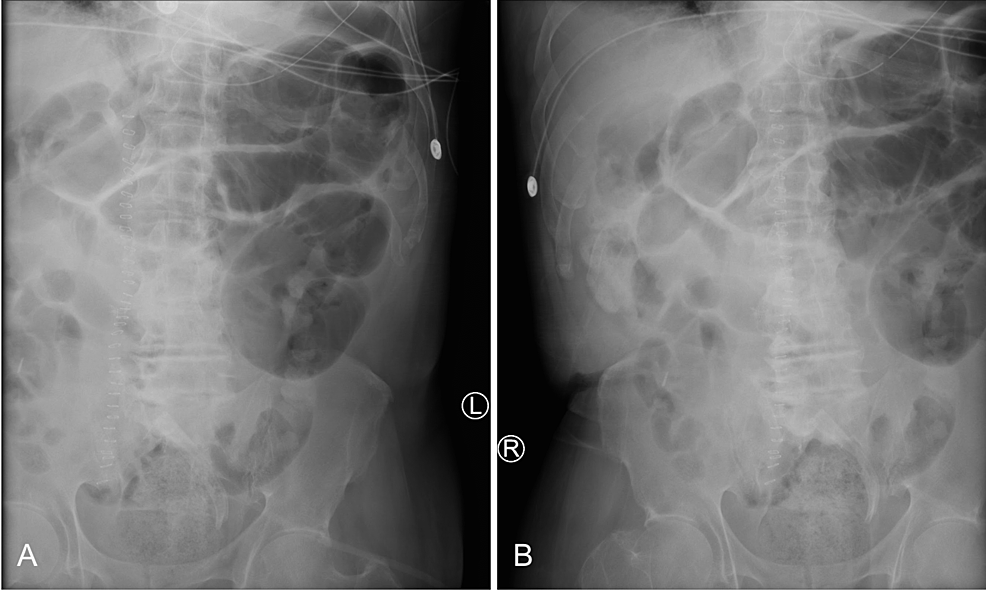

A small bowel series was performed and revealed delayed transit of contrast through the small bowel and dilated loops of the large bowel without enteric contrast, which was concerning for obstruction. Plain radiographs of the upper and lower abdomen prior to the administration of oral contrast can be seen in Figure 1.